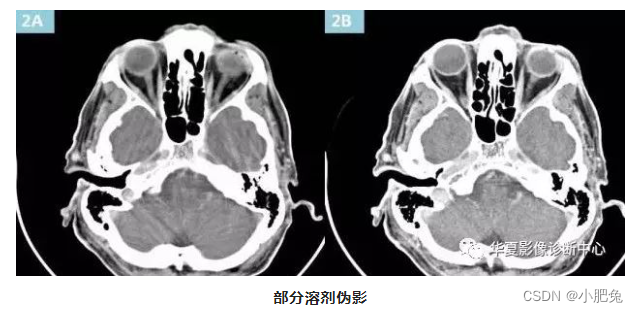

四、部分容积伪影

部分容积均化可导致部分容积效应并产生部分容积伪影 , 射线束产生只通过一种组织 , 得到的CT值就是该物质真实的CT值;若一束射线同时通过骨骼和空气, CT值就要根据这两种物质平均计算, 这种高原子序数或吸收系数大的物体,部分投影于扫描平面而产生的伪影被称为部分容积效应或部分容积伪影。 换言之 ,即被断层面内显示的并非是该物体的全部 , 其伪影的形状也可因物体的不同而有所不一样 , 一般在重建后横断面图像上可见条形、 环形或大片干扰的伪像, 部分容积伪影最常见和典型的现象, 是在头颅横断面时的颜部出现的条纹状伪影, 又被称为Hounsfield伪影(亨氏伪影),这种现象也与射线硬化作用有关。

左侧为5mm层厚的数据,可见明显的部分容积效应,右图为2mm的数据,薄层数据的部分容积效应明显减少。

处理方法

部分容积伪影抑制方法:采用薄层扫描或改变图像重建的算法;或采用容积伪影抑制扫描技术(VAR)可抑制该伪影。